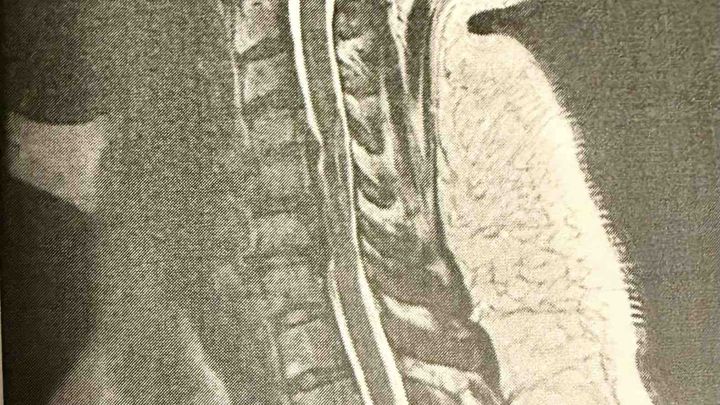

I’m disabled and homebound from a spinal cord injury and live with chronic pain and degenerative diseases.

Every day is a struggle, and I can’t perform daily activities of living. I have permanent nerve damage and lose feeling in my legs, feet and right hand. My right hand is partially paralyzed. I’m no longer able to drive or write, and have limited mobility.